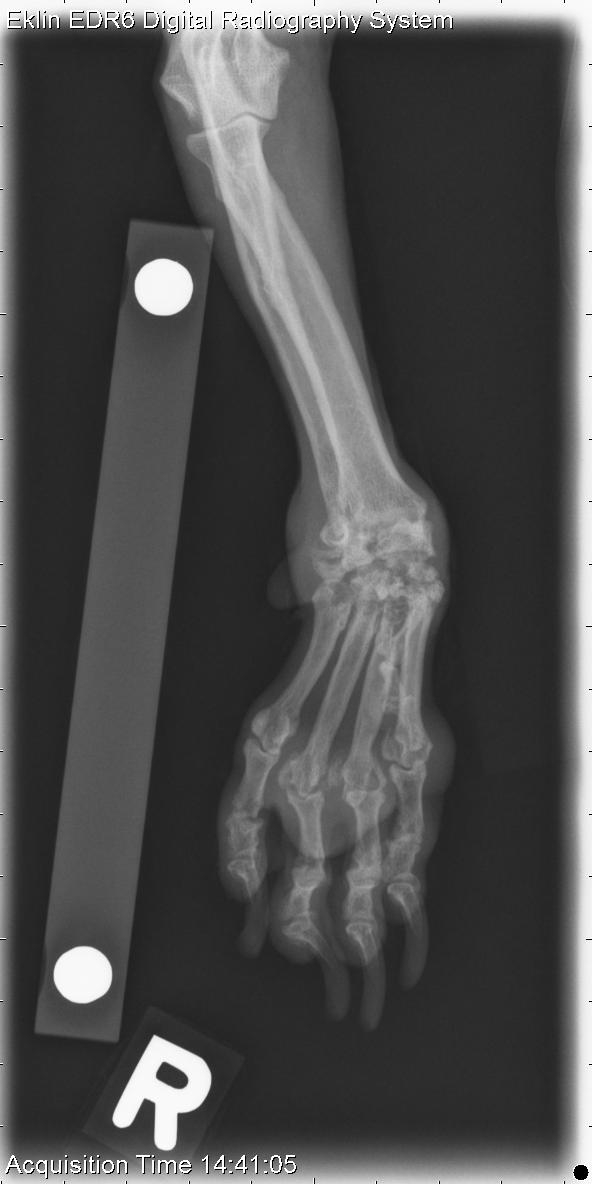

This case is a 9 year old female neutered Poodle cross presenting for carpal hyperextension. What is your radiographic diagnosis?

There is soft-tissue swelling surrounding both carpi. The carpal bones are misshapen, and there are multiple subchondral radiolucent regions. The left radial carpal joint is subluxated. Several interphalangeal and metacarpophalangeal joints are similarly affected.

Erosive polyarthritis with secondary osteoarthritis and joint instablility.